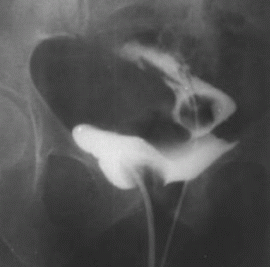

WYKONYWANIE CYSTOSKOPII (tj. OPTYCZNA OCENA WNĘTRZA PĘCHERZA MOCZOWEGO W ZNIECZULENIU MIEJSCOWYM LUB OGÓLNYM) WIZUALIZACJA ZA POMOCĄ KAMERY CYFROWEJ (ROZPOZNAWANIE BRODAWCZAKÓW, ZŁOGÓW, UCHYŁKÓW, POTWIERDZANIE BRAKU WZNOWY, KONTROLE PO LECZENIU)